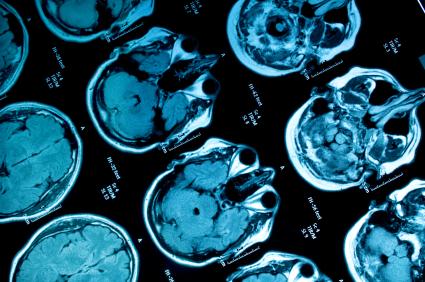

Студът увеличава с 48% риска от инсулт

Доплеровата сонография открива промени, които са настъпили в артериалното или венозното кръвообращение на мозъка. Виждат се атеросклеротичните плаки, стеснения в съдовете и запушвания. Това са част от сериозните рискови фактори за исхемичните мозъчни инсулти, които са около 80 – 85% от всички мозъчни инсулти. Кръвоизливите или хеморагичните мозъчни инсулти заемат около 15 – 20%. Ролята на доплеровата сонография, разбира се, правена от добър специалист и с качествена апаратура, е изключително важна, защото тя дава възможност да се оцени рискът.

Ако лекарят прецени, се правят и кръвни изследвания, за да се види нивото на кръвната захар, да се направи липиден профил, за да се види нивото на холестерола, оценява се и кръвното налягане. Вземат се предвид всички рискови фактори. Изследването продължава от половин до един час. Личният лекар дава направление за невролог, а той, ако след преглед установи, че има нужда, дава направление за доплерова сонография. Тя се прави на различни апарати. Диагностичните възможности са най-високи при цветнокодираната дуплекс-сонография, където директно могат да се визуализират кръвоносните съдове. Много добре се виждат атеросклеротичните плаки, стесненията, запушванията и това е от помощ за специалиста, който може да профилактира инсулта и той да не се случи. Ако има критична стеноза – висока степен на стеснение, има 2 алтернативи. Едната е операция, другата – разширяване на съда и поставяне на стент. В други случаи може да се предпишат медикаменти. Някои съвременни медикаменти могат да спрат нарастването на атеросклеротичните плаки и дори да ги редуцират. Необходима е комплексна оценка на рисковите фактори и индивидуална препоръка за всеки пациент.